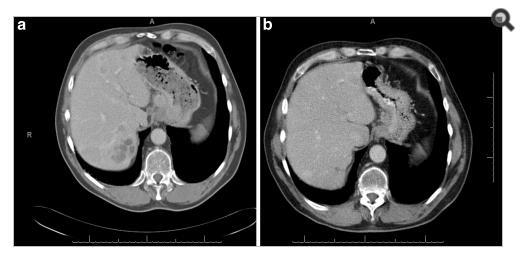

The tests were repeated for the patient again, general and comprehensive blood tests were performed and all agreed to a high levels of adrenal hormones in blood , radiographic images were also done in addition to magnetic resonance images throughout the body, the result of the tests and imaging was for the brain CT scan showed that there was no focal brain lesion and it was a metastatic spread test only, and no shift of midline structure and normal ventricular system, as the lumber spine CT showed that the findings were evidence of multiple bony lytic lesions seen in the lumber spine and sacral bone and no evidence of disc herniation or nerve root compression as showed in figure (7 ), this all tells that all back pains suffered by the patient were due to the presence of the tumor only .

The pelvic MRI showed that there were multiple hyper intense signals seen in the left ischium, that suggested bone metastasis while the abdominal MRI showed that there were a 6.75.3 cm right a adrenal mass lesion which appears isointense with thick wall moreover the neck Ultra sound showed a (97*11 ) mm nodule in the lift lobe with spots of calcification in the thyroid gland enlarged and indicating thyroiditis, after all of those critical signs shown through the previous medical scans , PET-CT scan was advised to insure the presence and the location of the primary lesions and the metasticitc spread , and after undergoing a PET-Ct scan the result showed a hypermetabolic and mostly malignant right adrenal mass with bone metastasis .

For Pet-Ct images taken for the patient pre and after the chemotherapy which shows no significant changes in the tumor distribution or size after chemotherapy.

nificant difference from the previous scan in 2004. (16- Jordanian medical services, PACS system and database store center).